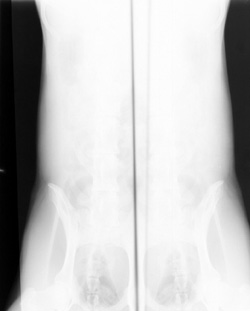

Film folded in cassette during exposure (double image